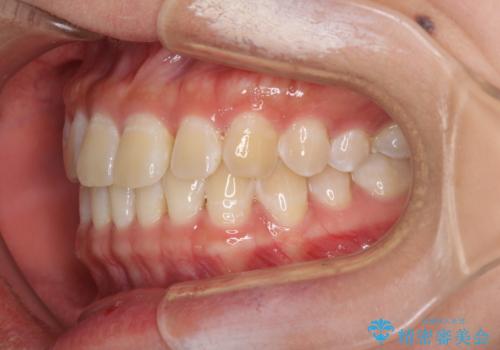

前歯の隙間と上下正中のズレを解消

- 上下前歯隙間と正中のズレを改善したいとのことで来院された患者様です。

自己管理を減らしたいとのことで、ワイヤー装置による矯正治療を行うこととしました。

正中がなかなか合わずに、2年近くの治療期間を要しました。